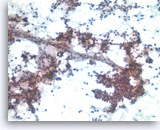

Acinar cell carcinoma,

Pancreas FNA, Cell Block.

The tumor cells are also focally positive for trypsin. Negative staining is found for neuroendocrine markers CD56, synaptophysin, and chromogranin, excluding the diagnosis of a pancreatic endocrine neoplasm. Despite the relatively bland appearance and the close resemblance to pancreatic endocrine neoplasms, acinar cell carcinomas are relatively aggressive tumors.

40X